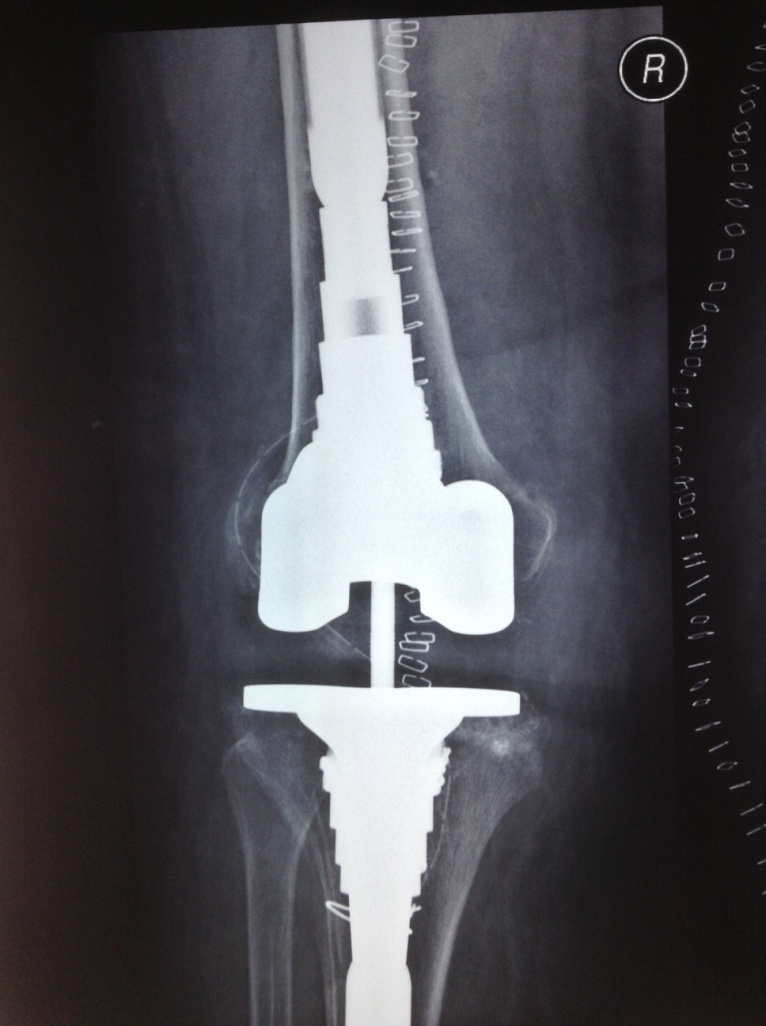

Revision Total Knee Replacement After a fructure

• Revision Total Knee Replacement After a fructure